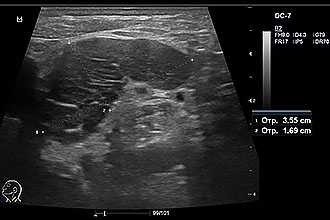

При исследовании щитовидной железы врач может визуализировать неоднородные очаги, дополнительные образования (узлы, кисты), уменьшение/увеличение размеров железы. При необходимости диагностика осуществляется в посттравматическом периоде для определения тяжести поражения, выявления месторасположения инородных тел.

Особенное внимание врач уделяет гипоэхогенным очагам (с пониженной плотностью тканей), так как подобные признаки могут указывать на злокачественное поражение. Что касается зон повышенного тканевой плотности - гиперэхогенности, можно заподозрить разрастание соединительной ткани.

При исследовании железистой ткани щитовидки врач акцентирует внимание на консистенцию и плотность, которая отображается на экране зонами различной плотности.